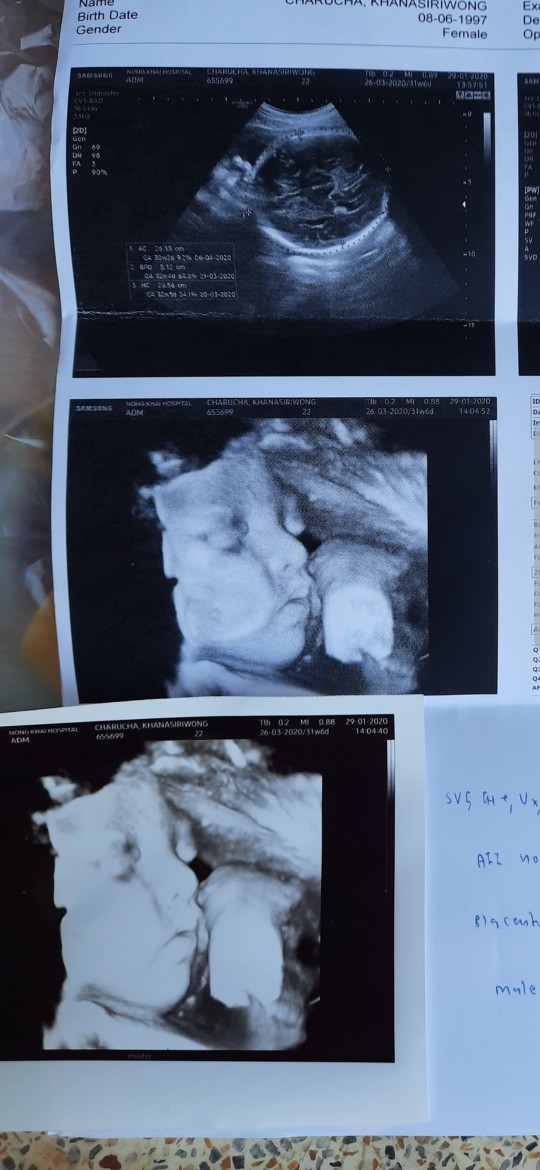

ทั้งกลัวทั้งตื่นเต้น

ปากนิดจมูกหน่อย แก้มเยอะจังนะลูก 25-26นี้ จะได้เจอกันแล้วนะคับ 2698g.

ของเค้าซาว 3มิติจ่ะ กำหนดคลอดปลายเดือนแต่น้องน้ำหนัก 2135g เอง ยังไม่กลับหัวด้วย😖

ตื่นเต้นมากคะ ยิ่งเห็นหน้าด้วย🥰🥰

ซาวกี่มิติค่ะเห็นชัดค่ะ

ไม่ทราบคะ ซาวแบบปกตินะคะ